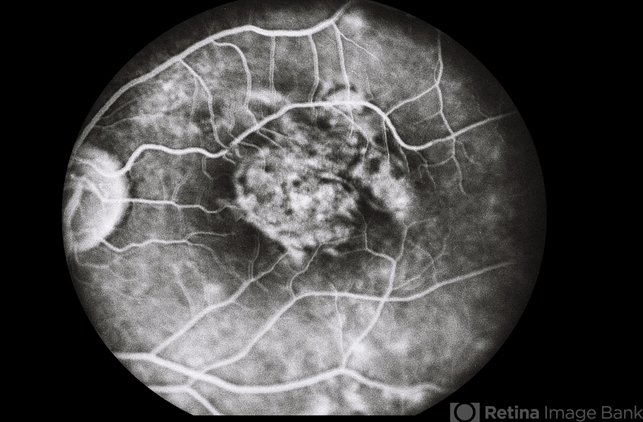

- No history. Fluorescein angiogram of the left eye showing no leakage in the macular area.